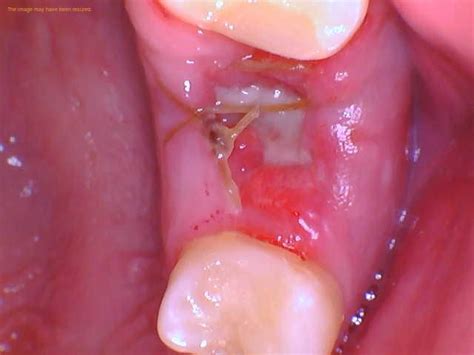

Wisdom Teeth Removal STITCHES Types of Stitches used in Wisdom Teeth

Wisdom Teeth Removal STITCHES Types of Stitches used in Wisdom Teeth from www.youtube.com

When dentists decide to stitch wisdom teeth extraction sites, they will use dissolvable stitches that do not require removal. These stitches are typically made from materials such as silk, gut, or synthetic polymers. The stitches will dissolve on their own over time, usually within a week or two. During the healing process, it is important to avoid disturbing the stitches, as this can lead to complications and delayed healing.